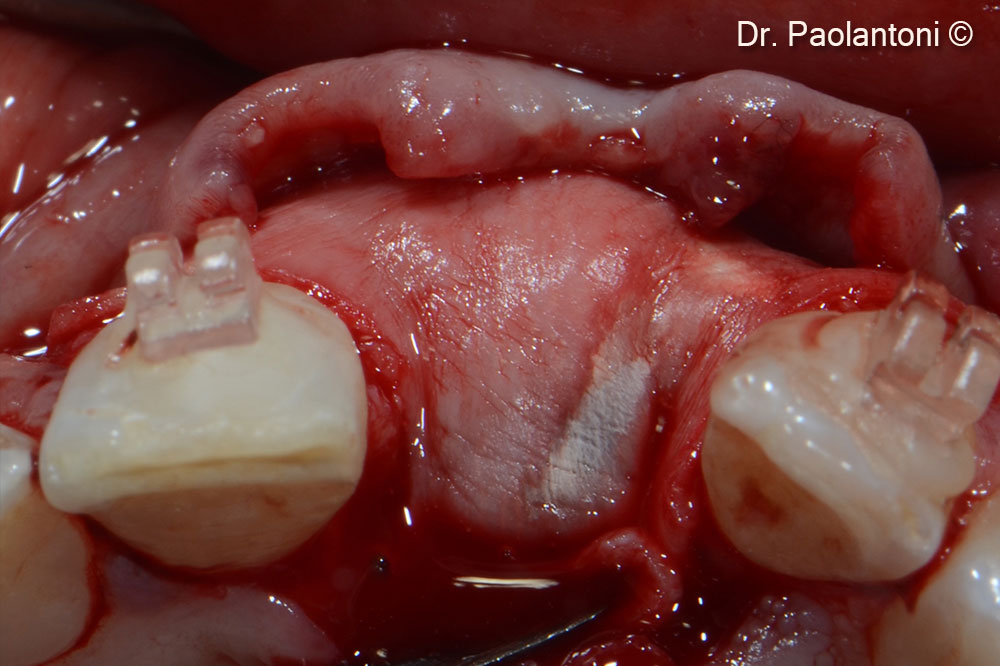

An Evolution collagen membrane is fixed with titanium pins

Flap clousure with 6.0 goretex suture